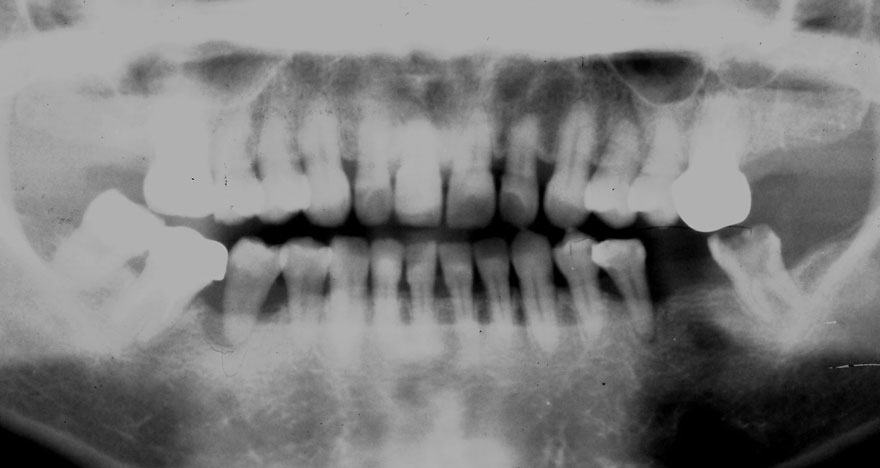

初診時 52歳 女性 平均歯槽骨喪失量:4.75mm

24年後 74歳

平均歯槽骨喪失量:6.13mm

21年間喪失量:-1.38mm

年間喪失速度:-0.057mm

(ケア頻度:1.25ヵ月ごと)